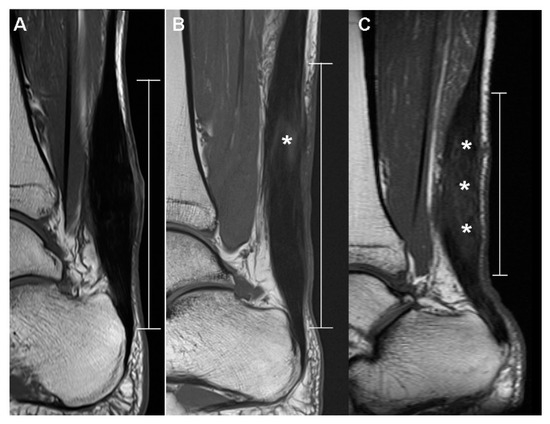

2.5.1. T1-Weighted Sagittal Image

| Dark SI artifact | 0.0063 | ||

| None | 3 (27.27%) | 0 (0%) | |

| Mild | 8 (72.73%) | 5 (45.5%) | |

| Marked | 0 (0%) | 6 (54.5%) | |